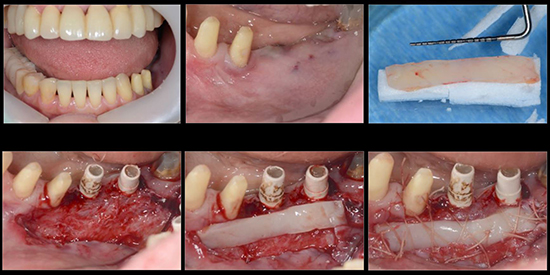

治療前01

治療前02

治療中01

治療中02

治療中03

治療中04

治療中05

治療中06